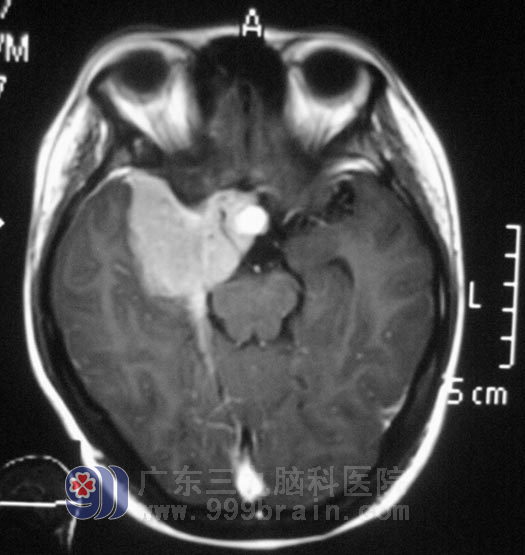

小李在2008年高考那年,出现右眼视力下降,以为是高负荷的复习迎考,造成视力出现问题。一年前右耳听力开始进行性下降,前十多天又出现了右耳失聪,外院行头颅MR检查提示:右侧眶内、中颅窝底、岩斜区占位,病变大小4.98cm×3.34cm×2.62cm,主要位于中颅窝,小部分累及后颅窝,脑干受压。

广东三九脑科医院综合神经外科 鲁明主任查阅影像资料发现:肿瘤侵润海绵窦,颅内外沟通,经CT检查见蝶骨及斜坡右侧、右侧颞骨岩部、额骨底部右侧骨质异常,经耳鼻喉科活检排除鼻咽癌。